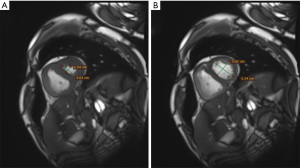

The interventricular septal angle, the angle between the apex of the ventricular septum and the upper and lower insertion points of the ventricular septum (68) (Figure 4A,4B), serves as both a diagnostic and prognostic marker in PH. A study has shown (52) that interventricular septal angle predicts combined pre-PH and post-PH with an AUC of 0.911. In addition, the interventricular septal angle predicts all-cause mortality in PH, which is of prognostic value. It was shown (53) that the interventricular septal angle was an independent predictor of mortality in PH-HFpEF (HR =1.48, P<0.001), and the resulting CMR prognostic model, which was based on interventricular septal angle and VMI, predicted mortality in patients with PH-HFpEF with an AUC of 0.76 (P<0.001).